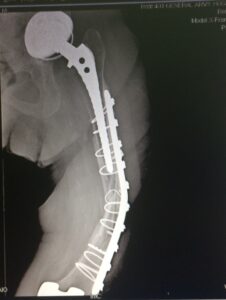

- Σε σοβαρά περιπροθετικά κατάγματα, στο επίπεδο αλλά και λίγο πιο μακριά από το άκρο του εμφυτεύματος της αρθροπλαστικής, γίνεται τοποθέτηση ειδικής πλάκας τιτανίου με κοχλίες +/- σύρματα.

- Εσωτερική οστεοσύνθεση με πλάκα με αλληλοεπικάλυψη των εμφυτευμάτων για να μην υπάρχουν υψηλές συγκεντρώσεις φορτίων (stress risers)

- H οστεοσύνθεση σε οστεοπορωτικoύς ασθενείς αρχίζει από το γόνατο με σωστή εφαρμογή του εμφυτεύματος και φθάνει μέχρι το ισχίο για να μην υπάρχουν stress risers.

Tα περιπροθετικά κατάγματα σε ηλικιωμένους πρέπει στην οστεοσύνθεση να περιλαμβάνουν ολόκληρο το μήκος του οστού, με αρκετή ελαστικότητα, προάγοντας έτσι την πώρωση και διατηρώντας ταυτόχρονα την σταθερότητα του συστήματος.